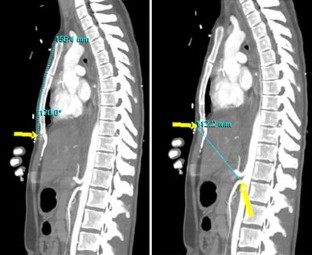

Fig. 1